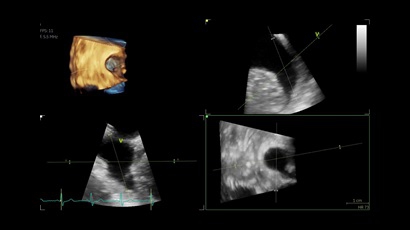

• Vivid IQ 4D с поддержкой технологии объемной реконструкции

• Передовые технологии, такие как 4D чреспищеводная эхокардиография, ЭКГ, стресс-эхо, внутрисердечная ультразвуковая эхокардиография, тканевый доплер и другие.

4D:

Да

• Режимы: 4D, 2D (B-режим), цветной допплеровский режим, режим энергетического допплера, M-режим, цветной M-режим, спектральные режимы импульсно-волнового допплера (PW) и непрерывно-волнового допплера (CW), визуализация скорости движения тканей.

• 4D AUTO AVQ - модуль автоматического выравнивания, сегментации и обсчета размеров кольца аортального клапана по объемным данным.

• 4D AUTO LVQ - модуль расчета массы миокарда ЛЖ на основе данных 4D-исследования.